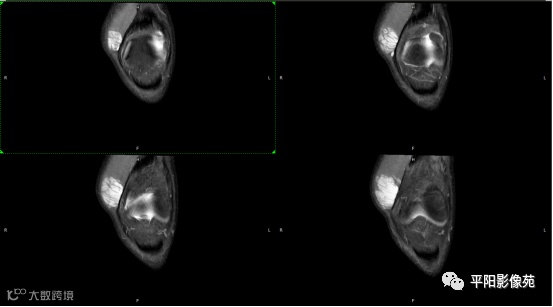

影像表现:

左膝关节股内侧肌内见多房样短T1长T2信号,内可见分隔,增强扫描明显强化,分隔未见明显强化,病灶局部与股骨远端分界不清。

MRI表现:好发于下肢, 较大病灶多为与肢体长轴一致的梭形, 边缘不清, 较小病灶呈类圆形, 边缘较清;②T1WI呈等或稍高信号, 病灶内部或边缘可见线条状或花边状高信号灶, 类似于皮下脂肪信号, T2WI上为明显高信号, 为本病特征性MRI表现;③病灶内静脉石及血管流空影为又一特征MRI表现;④GD-DTPA增强, 病灶明显强化, 其内低信号间隔无强化;⑤可见骨外形改变, 骨质增生及骨质吸收等表现。